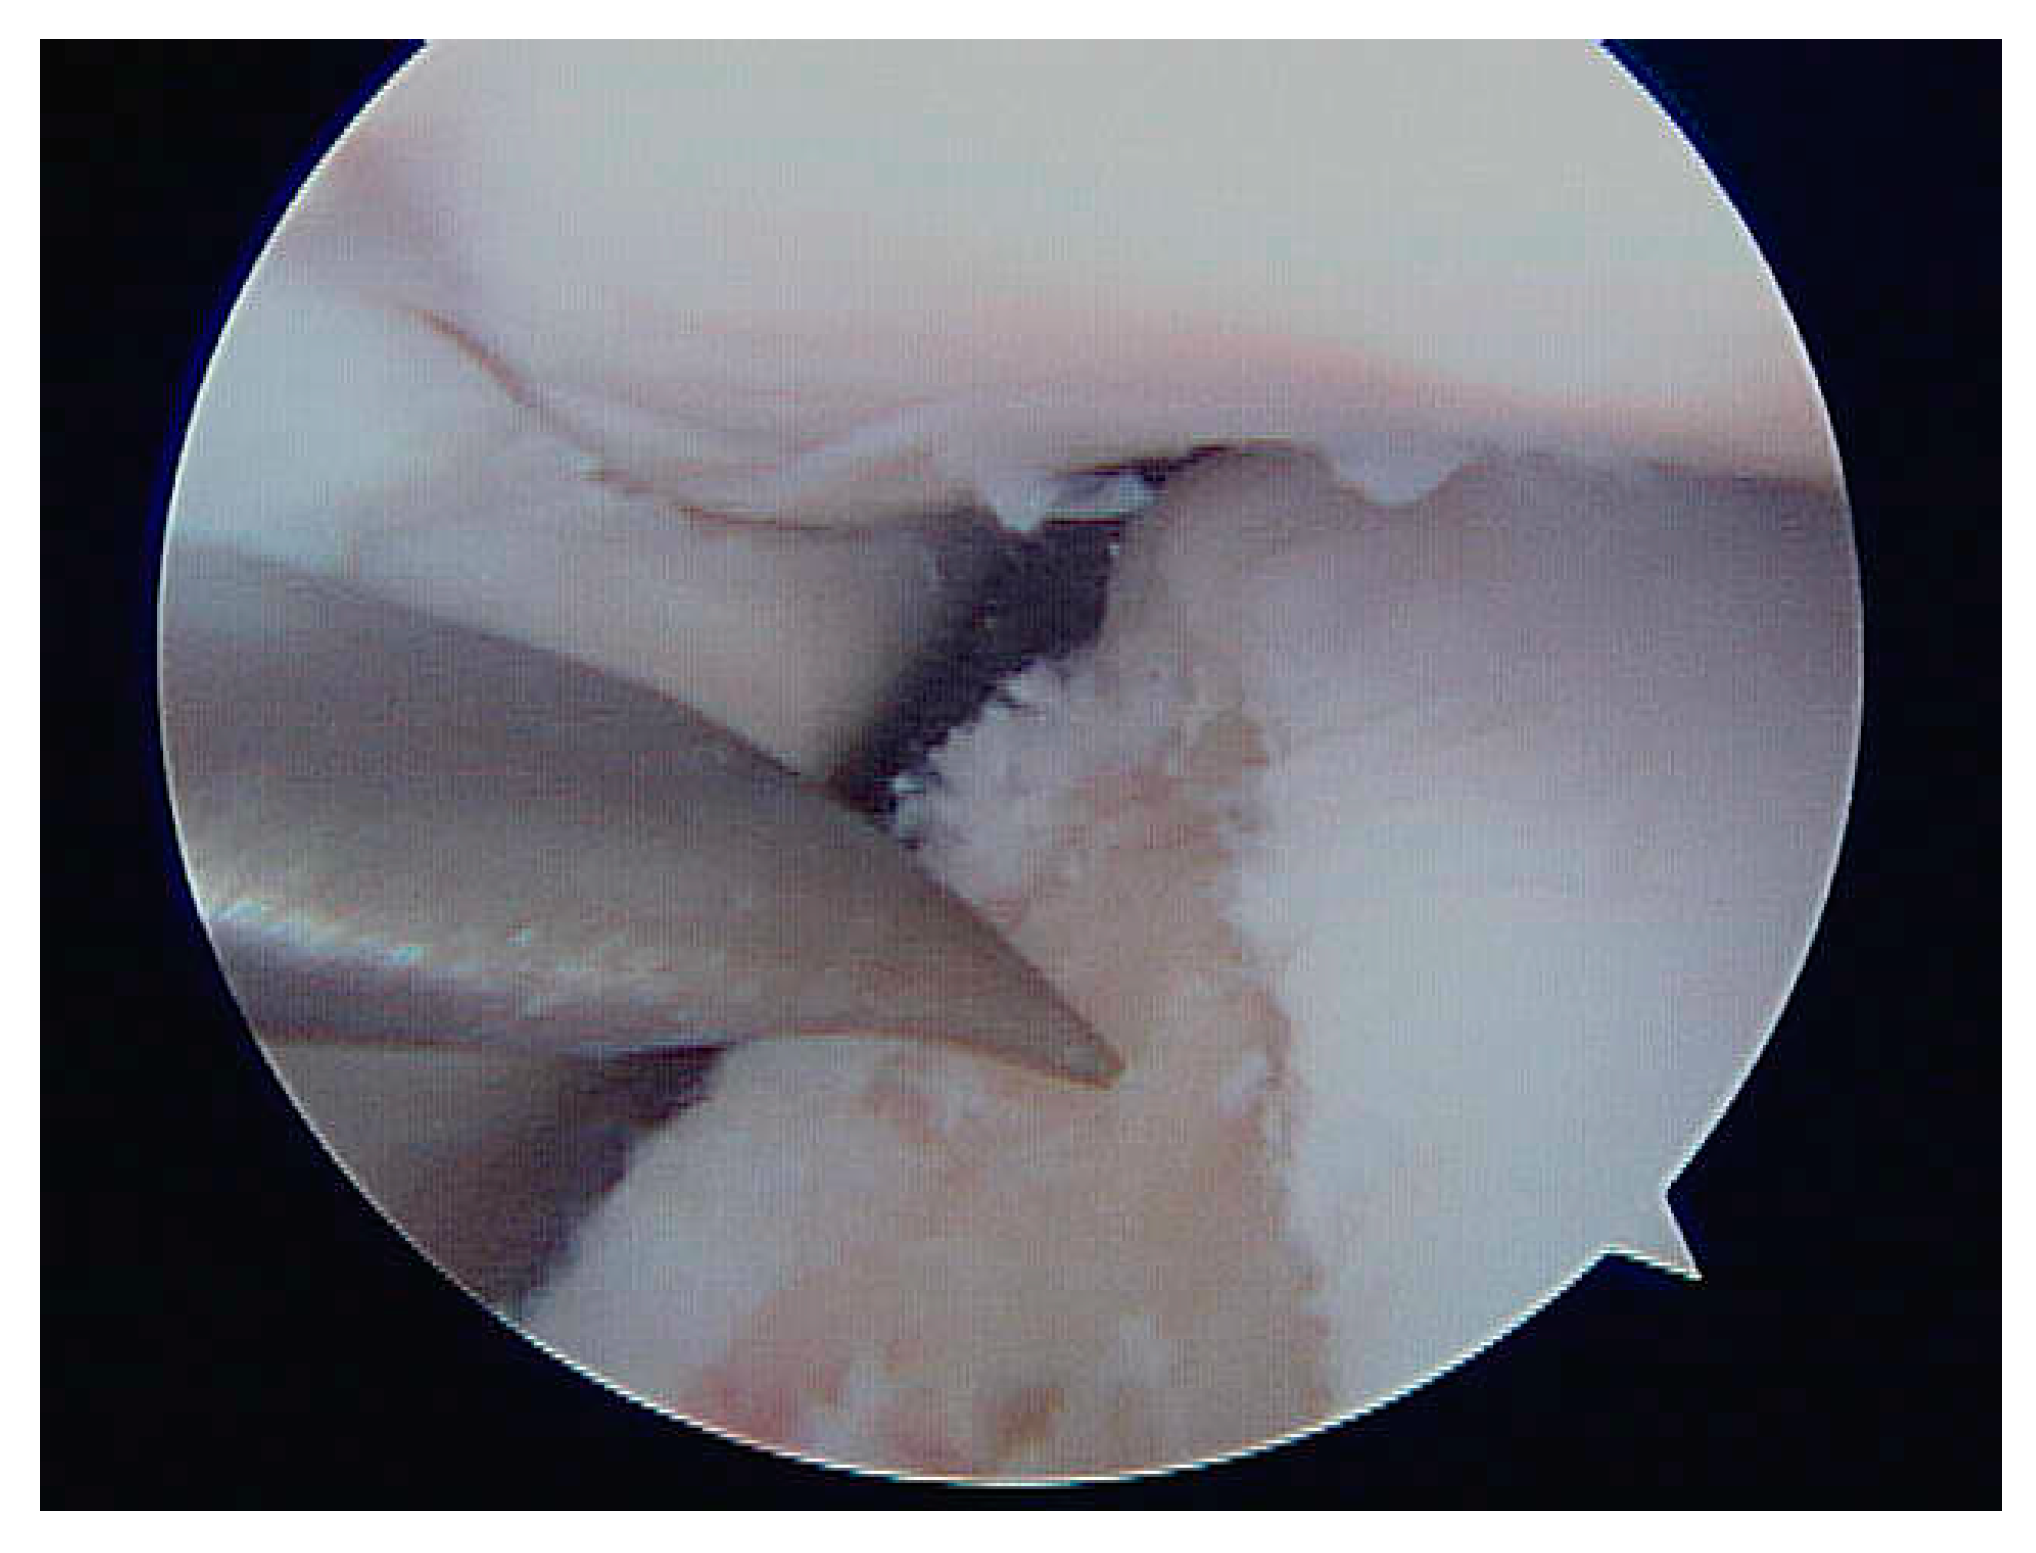

- Loss of gloss of the articular surface (Figure 1)

- Softening of the articular surface (Figure 2)

- Articular surface fibrillation (Figure 4)

- Partial erosion of the articular surface (Figure 5)

- Complete erosion – (damage of calcified layer) on the articular surface (Figure 6)